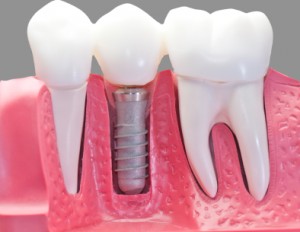

IMPLANTES Y PROTESIS

Los implantes dentales son unas raíces artificiales creados para sustituir dientes perdidos, capaces de integrarse, hasta el punto de convivir de forma sana y totalmente natural con los tejidos de la boca. Actualmente están fabricados preferentemente de titanio químicamente puro y actúan como sustitutos de las raíces dentales. Tras su colocación dentro del maxilar o de la mandíbula, sirven para que una vez están oseointegrados, apoyen los nuevos dientes artificiales que van unidos a ellos, ya sea en forma de coronas o de prótesis. Los implantes de carga inmediata es la técnica que permite colocar la prótesis, ya sea unitaria o completa, en un solo día. El uso de implantes dentales de carga inmediata se ha convertido en todo un referente en tratamientos dentales para la recuperación de piezas perdidas, facilitando que recuperes no sólo tu salud bucal, sinó, tu increíble sonrisa!